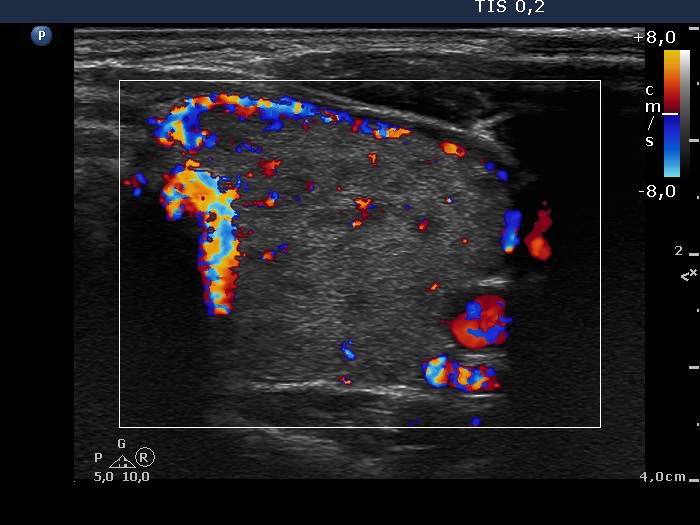

Consecutively operated patients with autoimmune thyroid disease - case 40 (888) (ultrasonographic picture 8)

Left lobe, transverse scan, color Doppler mode. The vascularization is a bit increased.